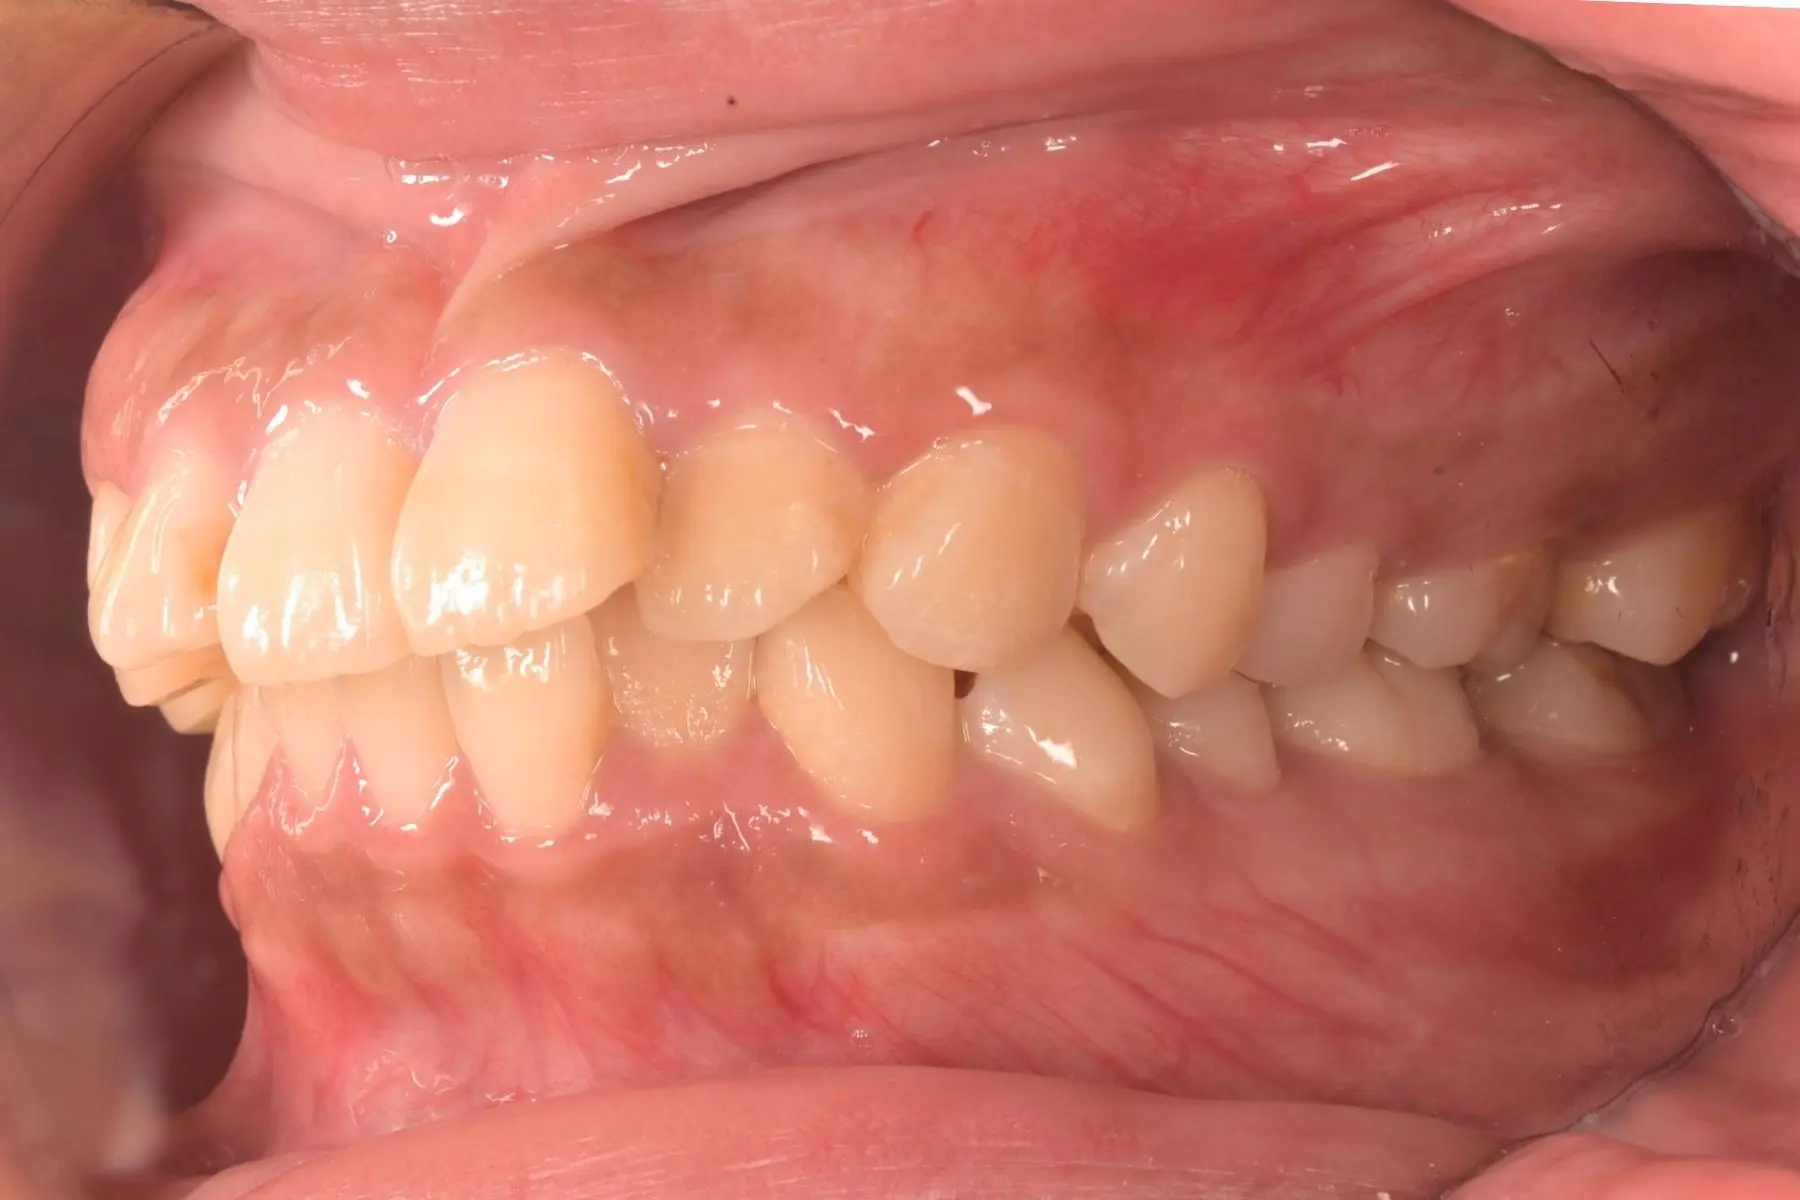

術前術後對比

自鎖式矯正_術前

自鎖式矯正_術後

我以前真的不太敢大笑,總覺得牙齒凸凸的、不好看。但現在不一樣了!在經歷了拔牙、骨釘、長時間配戴矯正器的過程後,牙齒逐漸整齊,嘴型也變得柔和自然。這段期間雖然不短,但每次看到牙齒慢慢變整齊,就覺得好值得。現在連側臉線條都順很多,整個人也更有自信了